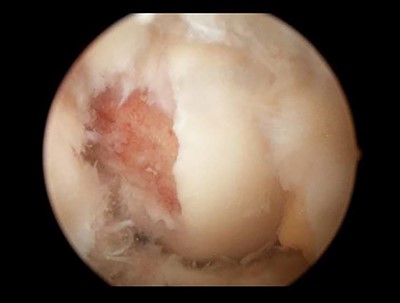

During arthroscopy, the ACL was torn proximally from the lateral femur condyle with an avulsion fragment. The lateral meniscus tear recognized on the MRI scan proved to be a double bucket handle lesion (Fig. 3). A partial lateral meniscectomy was performed and the insufficient ACL was debrided and removed along with the avulsion fragment.

Knee arthroscopy showed an avulsion fracture from the ACL of the lateral femoral condyle.